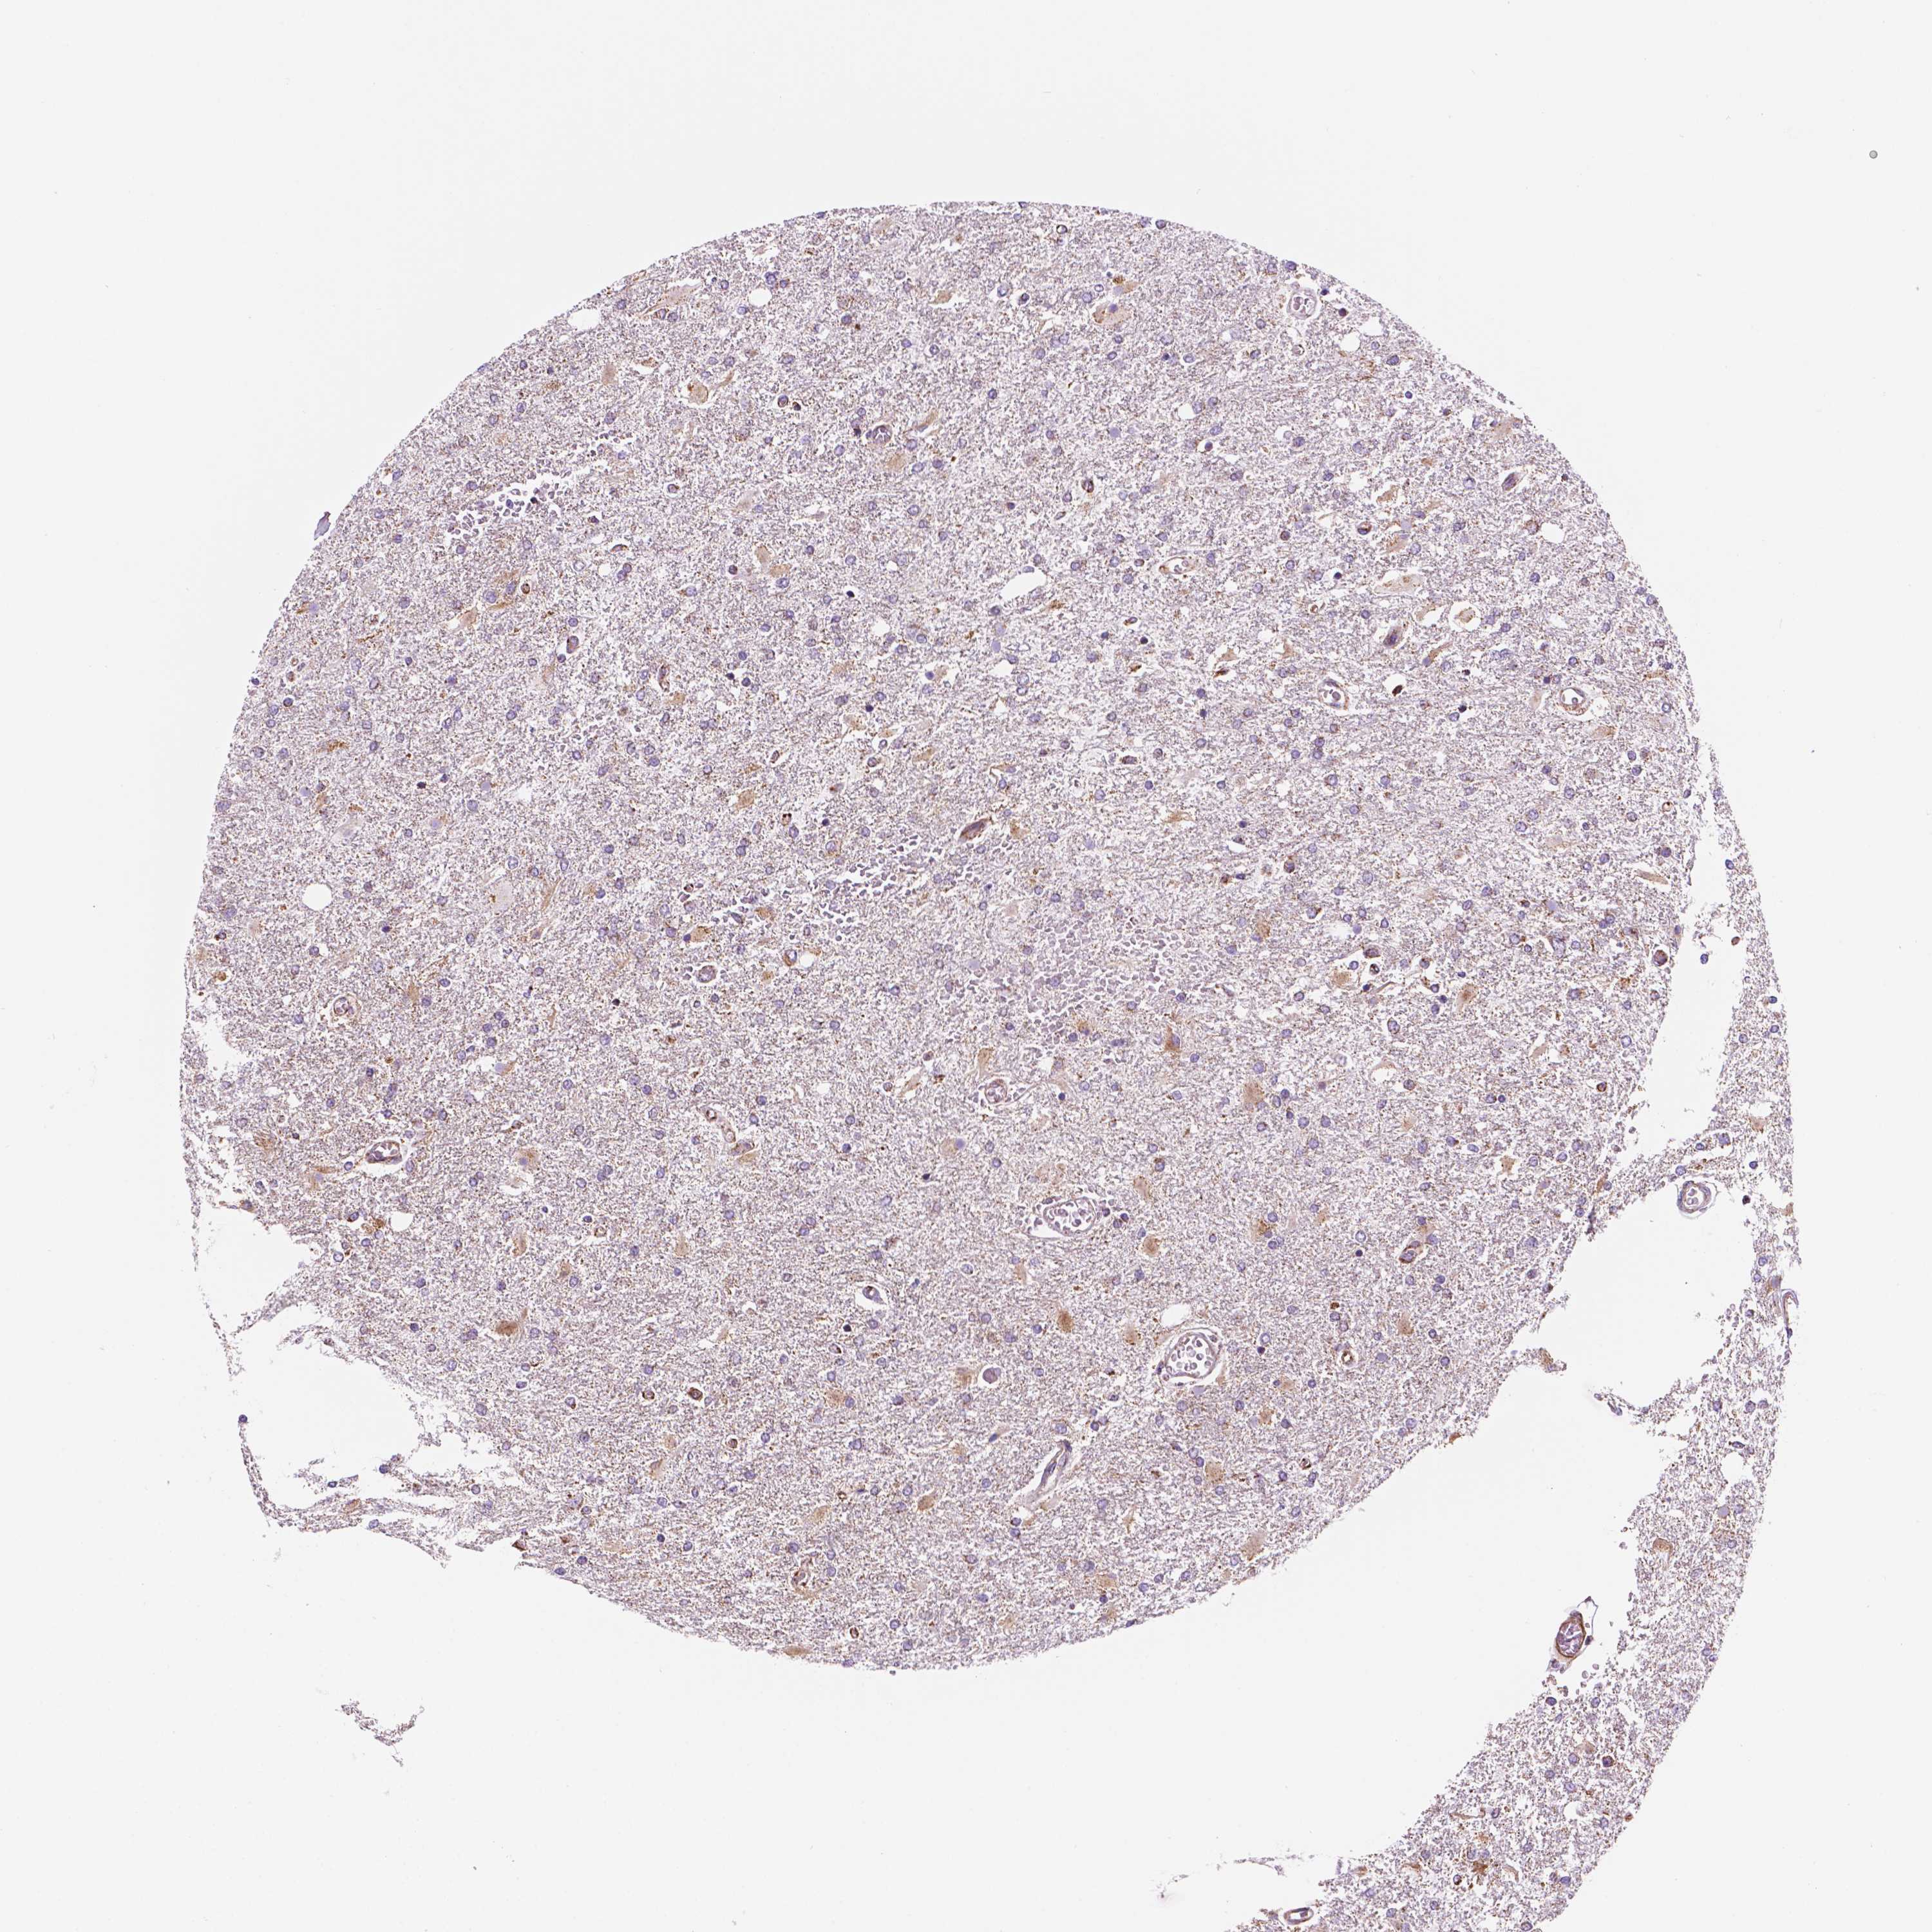

GLIOMA - Protein expressioni

A mouse-over function shows sample information and annotation data. Click on an image to view it in a full screen mode. Samples can be filtered based on level of antibody staining by selecting one or several of the following categories: high, medium, low and not detected. The assay and annotation is described here.

Note that samples used for immunohistochemistry by the Human Protein Atlas do not correspond to samples in the TCGA dataset.

Antibody stainingi

Antibody staining in the annotated cell types in the current human tissue is reported as not detected, low, medium, or high, based on conventional immunohistochemistry profiling in selected tissues. This score is based on the combination of the staining intensity and fraction of stained cells.

Each image is clickable and will lead to virtual microscopy that enables deeper exploration of all samples and also displays staining intensity scores, fraction scores and subcellular localization as well as patient and tissue information for each sample.

Antibody HPA067891

Staining

High

Medium

Low

Not detected

Intensity

Strong

Moderate

Weak

Negative

Quantity

>75%

75%-25%

<25%

None

Location

Nuclear

Cytoplasmic/membranous

Cytoplasmic/membranous,nuclear

Glioma, malignant, Low grade

Glioma, malignant, High grade

Glioma, malignant, NOS